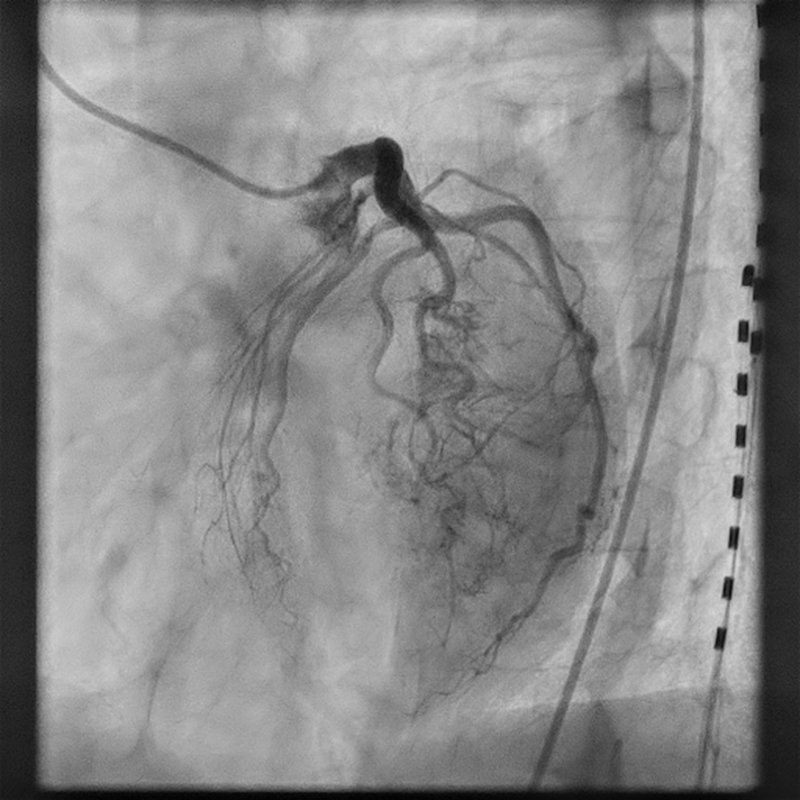

A 55-year-old woman with a history of hypothyroidism, chronic obstructive pulmonary disease, tobacco use, and anorexia nervosa was seen in the cardiology clinic for exertional chest pain and shortness of breath. A dobutamine stress test was recommended to evaluate symptoms of chest pain and shortness of breath. The stress echocardiogram was markedly abnormal, showing severe hypokinesis to akinesis in the mid-to-distal LAD territory with stress-induced decrease in ejection fraction (Videos 1 and 2). Therefore, she was referred for cardiac catheterization. On cardiac catheterization, she was found to have widely patent epicardial arteries with prominent Thebesian veins arising from a diagonal branch. There was significant shunting of the blood via a diagonal branch directly into the left ventricular cavity (Figure; Video 3).